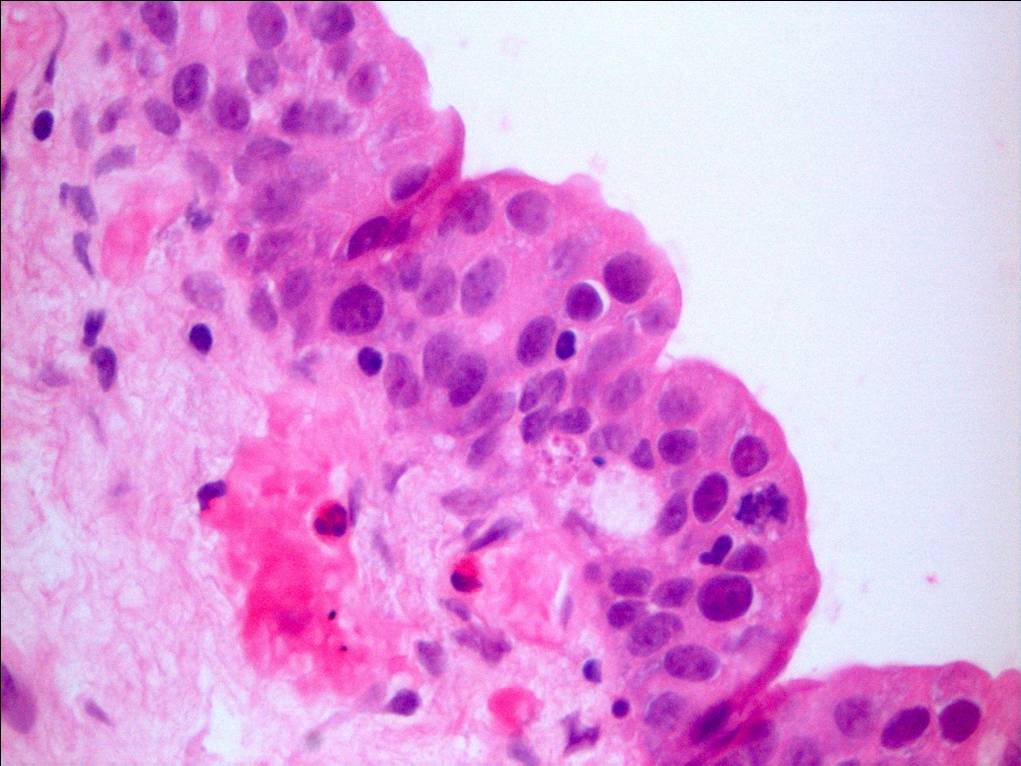

Bladder Flat Lesions

Case ID: 66

Reactive atypia

Atypia/dysplasia

Carcinoma in situ (CIS)